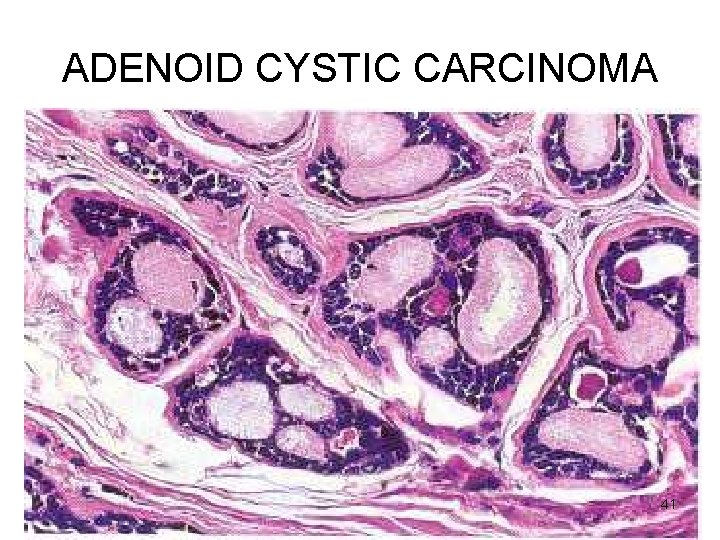

ADENOID CYSTIC CARCINOMA Microscopy • Small cells with dark compact nuclei, scanty cytoplasm • Arranged in tubules, solid, cribriform • SPACES BETWEEN CELLS FILLED WITH HYALINE MATERIAL – basement membrane material • Perineural invasion - pain 38

ADENOID CYSTIC CARCINOMA 41

ADENOID CYSTIC CARCINOMA CLINICAL ASPECTS • • Malignant Slow growing Stubbornly recurrent Painful – perineural invasion 42